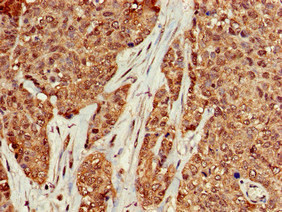

Immunohistochemistry of paraffin-embedded human ovarian cancer using CSB-PA13967A0Rb at dilution of 1:100